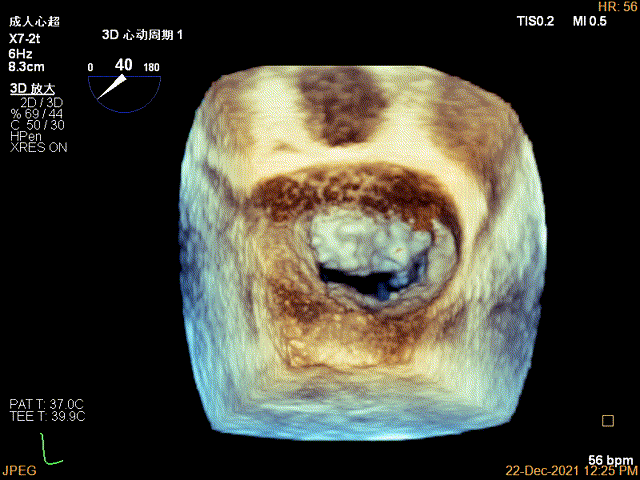

3D-VIEW验证前后叶抓捕情况,可观察到第一个夹子外侧的残余脱垂

3D-VIEW验证抓捕结果

1.这是一个巨大二尖瓣后叶脱垂治疗非常成功的经典案例,在术前评估中发现患者的脱垂的区域从P1到P3均有累及,主要病变在P2区,脱垂宽度达24.5mm,脱垂部位前后叶的长度尚可,术前判定适合两个长夹子(MCD0101: 夹臂长度 12mm,夹臂宽度4mm),因此术中在第一个夹子进行钳夹时,助手同步进行第二个夹子的测试,整个过程配合紧密流畅,缩短手术时间;

2.我们先放置第一个长夹子处理内侧P2区脱垂病变,夹合后MR明显减少,肺静脉血流频谱立刻转为正向,MV跨瓣压差在4mmHg,外侧区仍有残余脱垂以及少量分流,因此第二个夹子紧贴第一个夹子释放,避免两个夹子之间残余分流,也将术后瓣口狭窄的风险降到最低。

3.由于脱垂范围较大,第一个夹子放置后被残余脱垂掀动,活动度较大,第二个夹子置入时减少呼吸潮气量,与第一个夹子尽量平行靠紧,应用TEE 3D调整优化夹子方向和位置,同时在DSA上确认,让第二个夹子“点头下降“”,与第一夹子靠近同轴“比翼双飞”,尽可能多的抓捕后叶,夹闭后第一个夹子活动度好转,MR残余分流立刻减少到微量,确认MV跨瓣压差5mmHg, 效果满意。